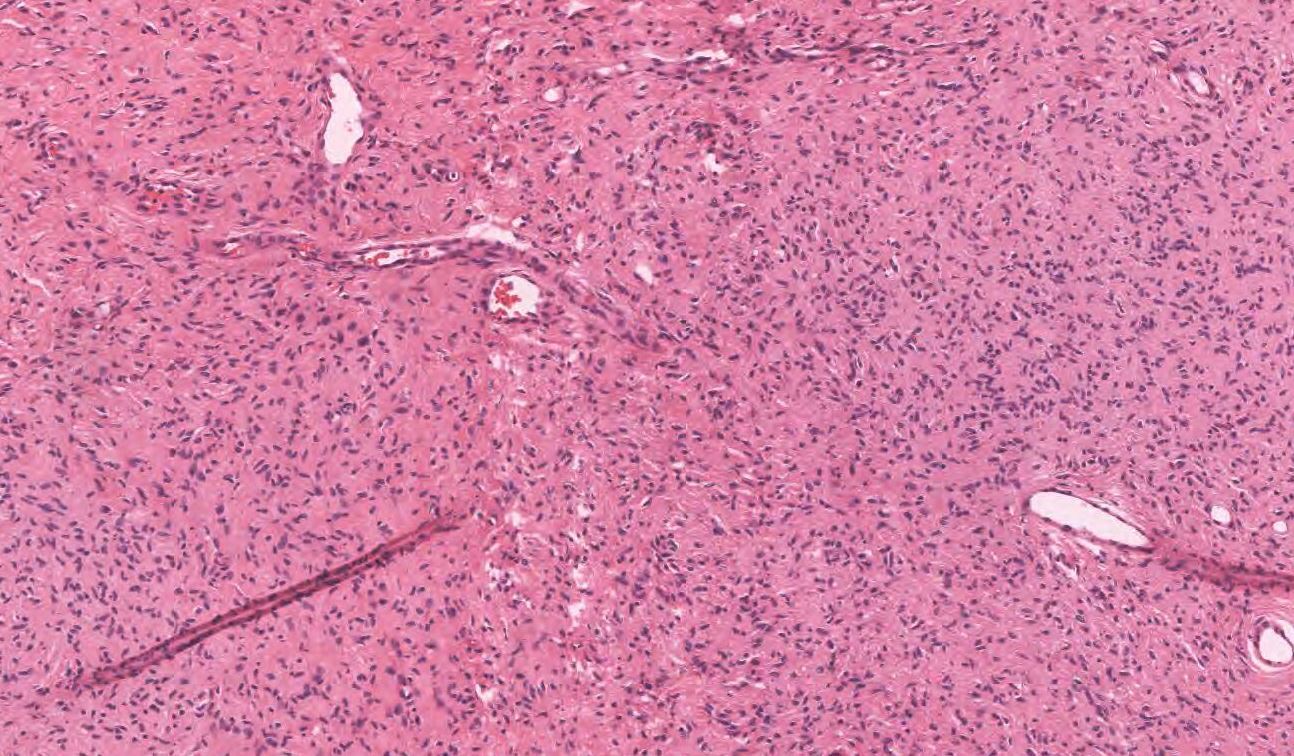

Cellular Blue Nevus